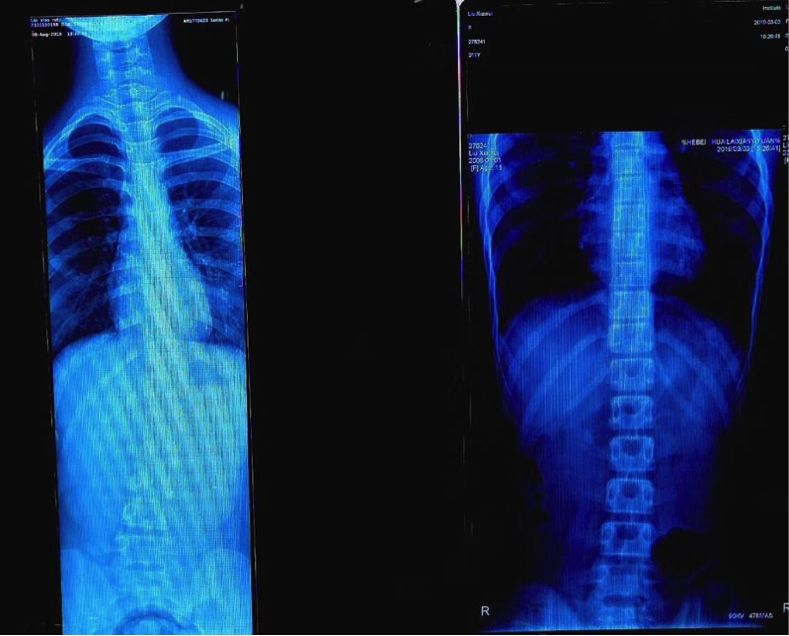

以上图片是我们之前训练的一个孩子,他经常练足球。片子显示脊柱侧弯已经达到左边这个图片的样子。经过差不多三个月的训练纠正,这个孩子的脊柱已经恢复得差不多了(右图)。

关于脊柱侧弯的训练方法,具体要看孩子脊柱是往哪一侧弯,需要训练加强对应侧的力量,包括肌肉的训练。